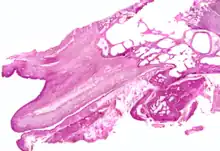

Frontal section through left ear; upper half of section